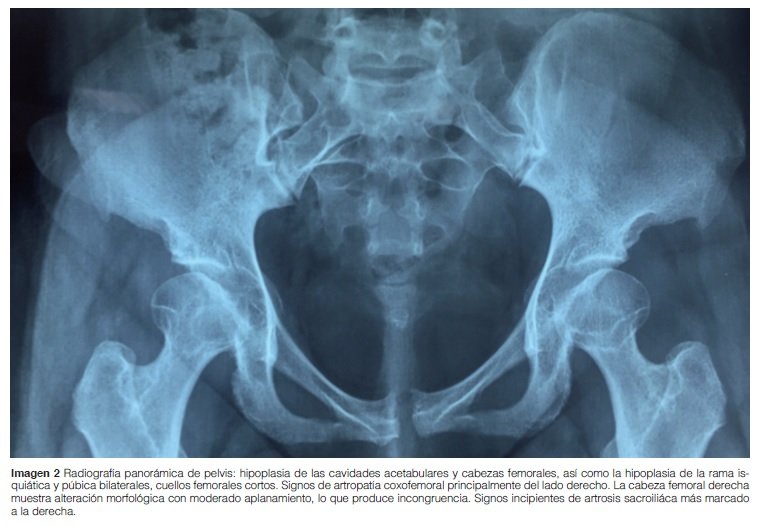

Caderas: Hipoplasia de las cavidades acetabulares y cabezas femorales, así como hipoplasia de la rama isquiática y púbica bilateralmente, los cuellos femorales cortos. La cabeza femoral derecha presenta alteración morfológica con moderado aplanamiento, lo que produce incongruencia (Imagen 2).